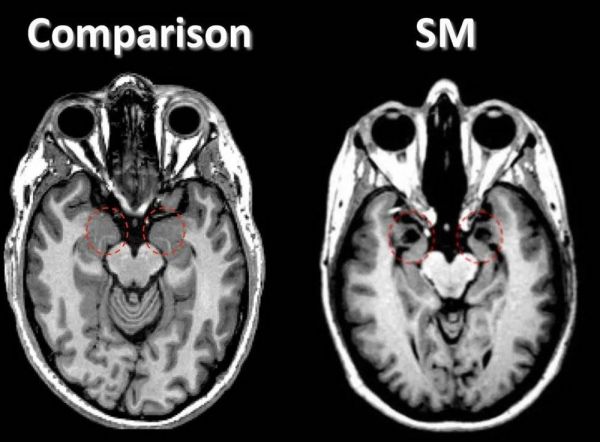

这种病变逐渐摧毁了S.M.大脑两侧的杏仁核——这一结构与情绪、记忆与决策密切相关,尤其对恐惧情绪的产生十分重要。S.M.在幼年时还会感到害怕,但从十几岁起,疾病就彻底夺走了她对恐惧的感知。除此之外,她依然能感受愉悦、悲伤等其他情绪,智力也保持在正常水平。

右侧为S.M.的大脑核磁扫描图像,左侧为健康对照,红色圆圈标出了大脑两侧杏仁核的缺失 | Iowa Neurological Patient Registry

1986年,在S.M.20岁时,神经科学家第一次遇到了这位不寻常的患者。在当时,她是人们发现的第一个此类病例。S.M.的杏仁核被疾病彻底破坏,但她脑内的其他结构却又保存十分完好——这种极为罕见的特征提供了探寻杏仁核功能的难得机会。